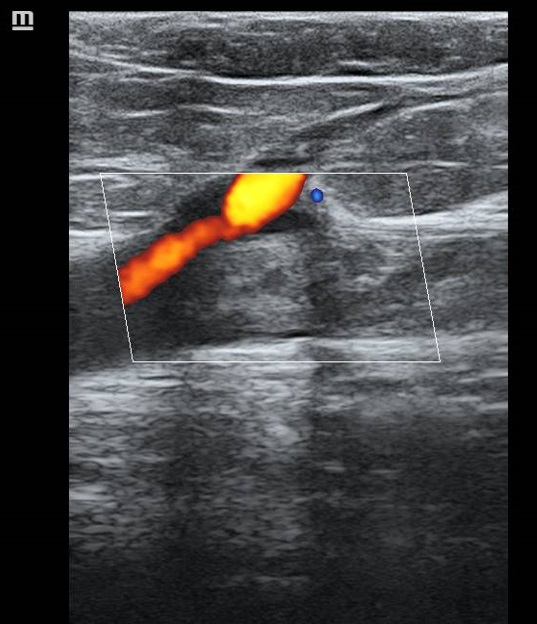

La ecografía pulmonar muestra microconsolidación y líneas B en campo posteroinferior derecho (imagen 1). Ante el antecedente de inmovilización y TEP previo, preguntamos por edemas y refiere inflamación en miembro inferior izquierdo, constatándose cierto aumento de perímetro. La ecografía de MII muestra trombo hiperecogénico femoropoplíteo con captación de Doppler periférico (imagen 2, 3 y 4).